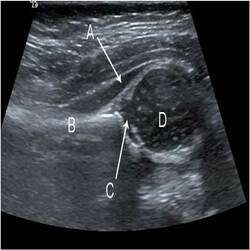

Ultrasonography Services